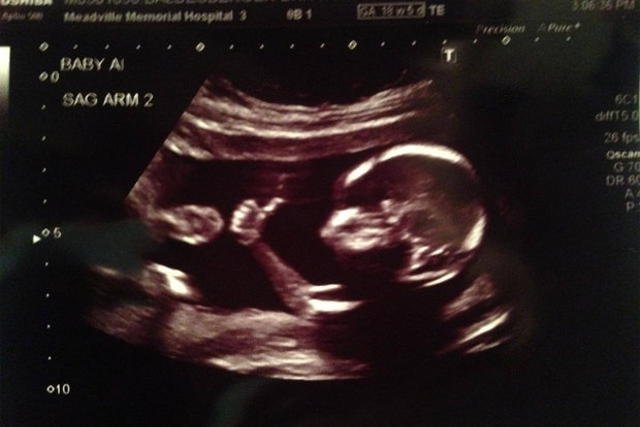

Uniesiony kciuk, wystawiony język, znak pokoju, a nawet znak szatana – podczas USG dzieci przyjmują różne pozycie oraz robią dziwaczne gesty. Czy chcą w ten sposób przekazać coś swoim rodzicom? Czy może rodzice widzą to, co chcą zobaczyć?

Ruchy dziecka są bardzo widoczne podczas USG. Często zdarza się, że widać całą dłoń. Rodzicom często wydaje się, że dziecko próbuje nawiązać z nimi kontakt, ale nie ma w tym sensu, nie stoi za tym żadna treść.

Oczywiście większość rodziców zdają sobie sprawę z tego, że ułożenie dłoni dziecka np. w znak pokoju to jedynie naturalne, niekontrolowane jeszcze ruchy małego człowieka. Ale czy nie milej żyje się w przekonaniu, że "Mój syn mi pomachał"?

Widząc ruchy dziecka podczas badania, nasza wyobraźnia podpowiada nam to czego tak naprawdę nie można wyczytać z obrazu USG. A to wszystko dlatego, że rodzice podchodzą do tego bardzo emocjonalnie. W przypadku kobiet wydziela się wiele hormonów, które wpływają na naszą reakcję, dlatego w taki sposób matki interpretuję zachowanie dziecka.